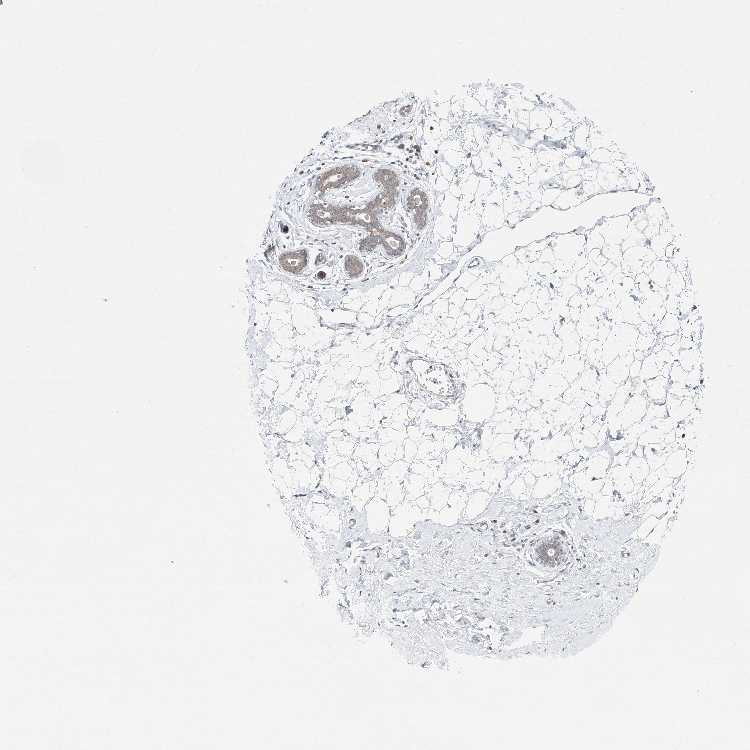

BREAST - Antibody stainingi

Antibody staining in the annotated cell types in the current human tissue is reported as not detected, low, medium, or high, based on conventional immunohistochemistry profiling in selected tissues. This score is based on the combination of the staining intensity and fraction of stained cells.

Each image is clickable and will lead to virtual microscopy that enables deeper exploration of all samples and also displays staining intensity scores, fraction scores and subcellular localization as well as patient and tissue information for each sample.

Antibody HPA034806

Adipocytes Not detected

Glandular cells Medium

Myoepithelial cells Low